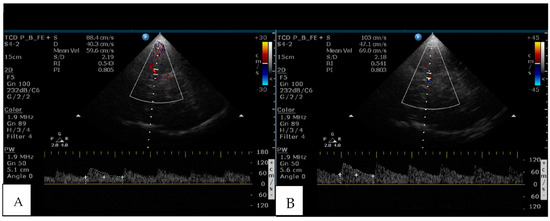

- Markus, H.S.; Harrison, M.J. Estimation of cerebrovascular reactivity using transcranial Doppler, including the use of breath-holding as the vasodilatory stimulus. Stroke 1992, 23, 668–673. [Google Scholar] [CrossRef]

| RI | 0.55 ± 0.09 | 0.58 ± 0.11 | 0.52 ± 0.06 | 0.021 |

| PI | 0.84 ± 0.22 | 0.91 ± 0.26 | 0.76 ± 0.12 | 0.005 |

| BHI | 0.71 ± 0.51 | 0.53 ± 0.31 | 0.91 ± 0.62 | 0.000 |

| Vma cm/s (M ± SD) | 48.6 ± 11.1 | 44.32 ± 9.0 | 53.42 ± 11.4 | 0.003 |

| cVR n (%) yes = BHI < 0.69 | 27 (52.9) | 18 (66.7) | 9 (37.5) | 0.037 |